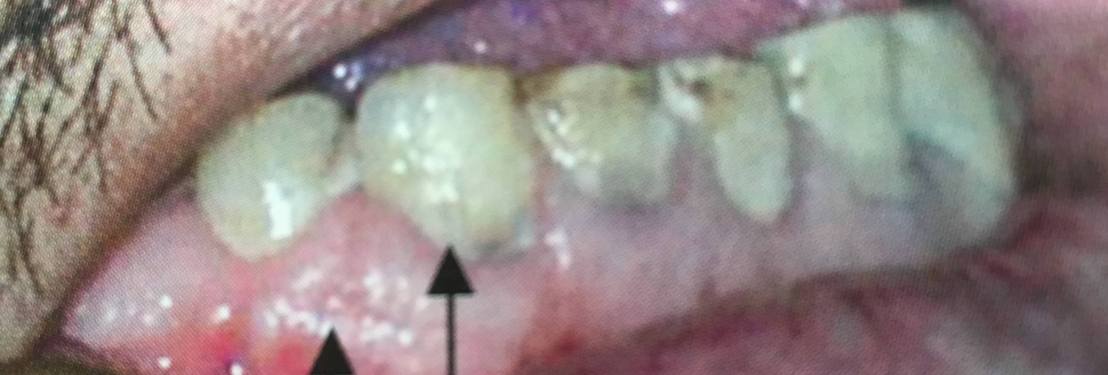

แสดงรอยโรคในช่องปากและมุมปาก

ดูที่ lip commissure ใกล้ๆ